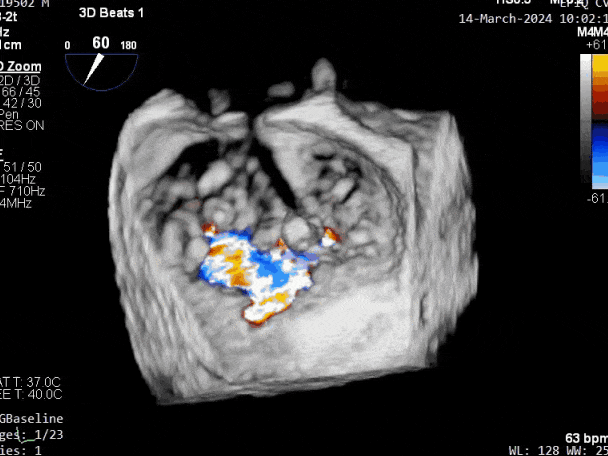

二尖瓣后叶活动受限,呈房源性栓系,以P3区为重,二尖瓣前叶假性脱垂,二尖瓣瓣环前后径49mm,左右径40mm。

PISA法测r=12mm,EROA=0.72cm2,RVOL=100ml,RF 26%。LVEDD 57mm,左房71*59*77mm,右房55*69mm,LVEF 70%。

二尖瓣反流(重度,4+级,Carpentier I型)

第三个瓣膜夹释放后评估,释放后评估,二尖瓣呈双孔,组织桥张力合适,瓣膜夹轴向与二尖瓣闭合线垂直,无残余反流

2. 本例患者外院超声心动图考虑二尖瓣前叶脱垂,入院后经食道超声心动图明确该患者为二尖瓣后叶活动受限,呈房源性栓系,二尖瓣前叶假性脱垂,超声特征表现为心房功能性二尖瓣反流终末期,呈现出很典型的二尖瓣后瓣环向左室游离壁顶部位移和后叶挛缩表现,同时合并有明显的二尖瓣瓣环扩张、圆形化,左房增大等不利因素,术中通过精准的影像指导和手术操作,成功行TEER,二尖瓣反流程度减轻至微量。